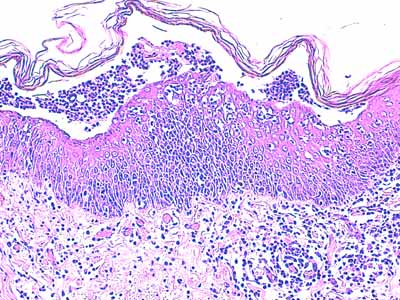

Photo 11 (Hémalun-Eosine X400) : Vue rapprochée d’une pustule intra-épidermique sous-cornée :

son toit est fragile formé de fines lamelles de kératine; son plancher épidermique

est le siège d’une forte exocytose de cellules inflammatoires; elle renferme

des granulocytes et quelques cellules épithéliales arrondies de type acantholytique.

Légendes de la Photo 11 :

- Pointes de flèche jaune : toit de la pustule intra-épidermique sous-cornée, composé de fines lamelles de kératine orthokératosique alvéolaire

- Étoile rouge évidée : cellule épithéliale acantholysée (la plus grande

- Pointes de flèche turquoise : elles délimitent le contour du plancher de la pustule intra-épidermique sous-cornée

- Flèche orange : spongiose ou œdème intercellulaire

- Étoiles vertes évidées : granulocytes dans le contenu de la pustule et en cours d’exocytose transépidermique dans le plancher épidermique

- Cercles jaunes : pustules micro-loculaires qui confluent en position sous-cornée pour former la pustule dont le plancher est matérialisé par les pointes de flèche turquoises

- Double flèche noire : épiderme

- Double flèche pointillée noire : derme